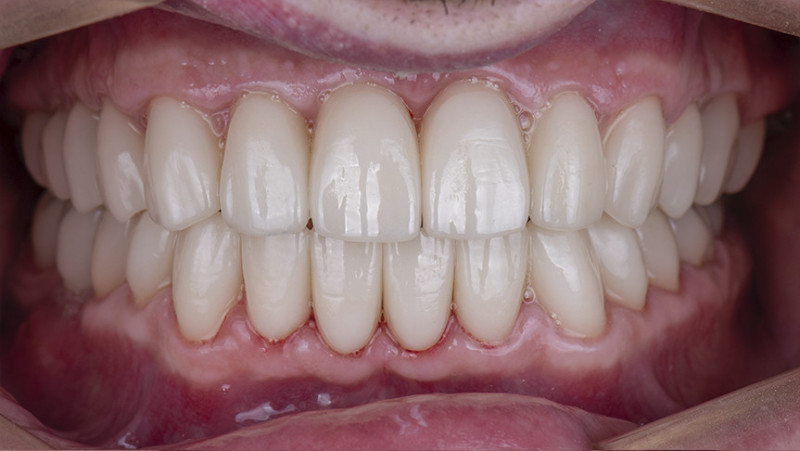

Установка керамической коронки

Изготовили и установили 22 керамические коронки EMAX и 6 виниров на нижнюю челюсть. Провели пластику десны в области 22 зуба. Устранили сильную рецессию десны в области имплантата, установленного в другой клинике.